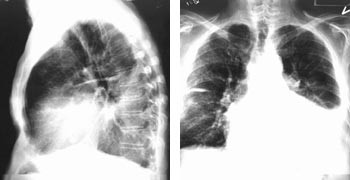

Etter punksjon av v. subclavia og innsetting av veneintroduser, innføres en lang ledesonde til høyre atrium under røntgengjennomlysning, oftest i flere plan. Over ledesonden innføres et spesiallaget introdusersystem med en 40 – 45 cm lang introduserhylse over en 54 cm lang dilatator til sinus coronarius. Etter at introduseren er plassert i stabil posisjon i sinus coronarius, innføres et 80 cm langt venografikateter med en lateksballong ved tuppen på kateteret til sinus coronarius. Denne ballongen kan blåses opp til en diameter på 10 mm og okkludere sinus coronarius helt eller delvis mens man injiserer kontrast og tar røntgenbilde av koronarvenene. Koronarveneanatomien har vist seg å variere fra pasient til pasient. Venogrammet gir et bilde av hvilke vener som er tilgjengelige for plassering av pacemakerledningen (fig 1). Man tilstreber å få spissen av pacemakerledningen plassert distalt i en lateral koronarvene. Til tross for spesielle vinklinger av ledningen er det ofte meget vanskelig å få plassert spissen på ledningen i ønsket posisjon. Kriteriene på en god posisjon av ledningen er at terskelen for stimulering av venstre ventrikkel ved 0,5 ms pulsvarighet er maksimum 3,0 V og at R-bølgen> 4,0 mV. Det må ikke forekomme stimulering av n. frenicus med diafragmastimulering ved høyeste spenning 7,5 V. Elektrogrammet avledes fra ledningen i koronarvenen og elektrogrammets konfigurasjon avgjør om ledningen er korrekt plassert over venstre ventrikkel.

Metode

For å innføre pacemakerledning til koronarvener kreves erfaring i hjertekateterisering. Man må ha mulighet for venografi av koronarvenene (fig 1). Ofte kan ikke de laterale koronarvener påvises ved venografi (15). Prosedyren som krever gjennomlysning i flere plan, tar fra en time til 4 – 5 timer. For våre fem pasienter var gjennomsnittlig prosedyretid 187 ± 40 minutter. Dersom man ikke får ledningen langt nok perifert i koronarvenen, kan den forskyve seg sentralt, noe som vil kunne føre til stimuleringssvikt (pasient 5) og eventuelt også til stimulering av n. frenicus med diafragmarykninger som konsekvens.